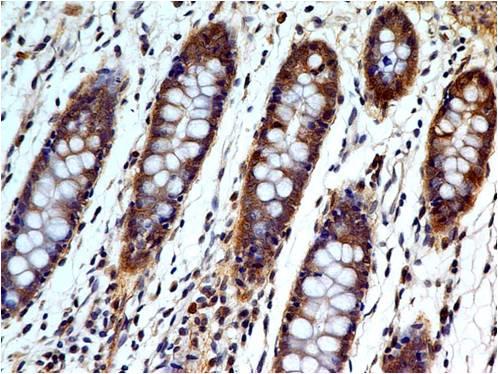

Figure 1: Immunohistochemistry of paraffin-embedded sections (kidney) Figure 1: Immunohistochemistry staining of human kidney (paraffin-embedded sections) with anti-cytokeratin 18 (C-04).

Immunohistochemistry (paraffin sections): Recommended dilution: 10 μg/ml; positive control: colon, kidney.

| Tissue Specificity: | Expressed in colon, placenta, liver and very weakly in exocervix. Increased expression observed in lymph nodes of breast carcinoma. |